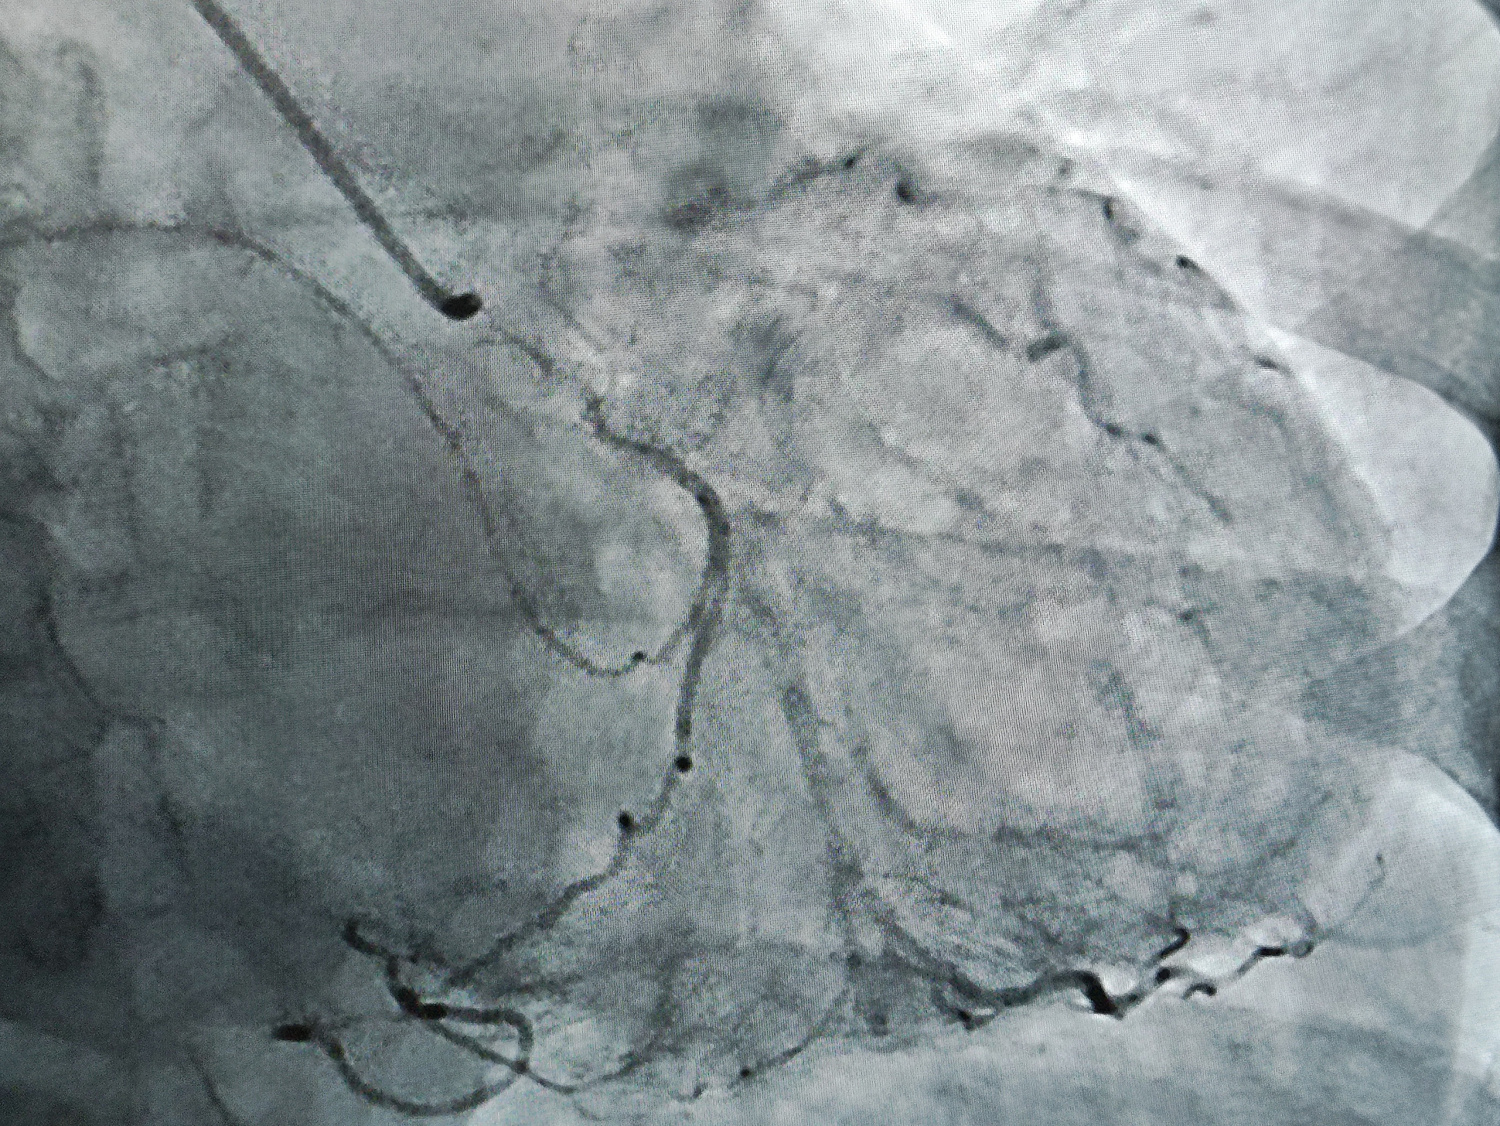

Первую коронарографию пациентке с ишемической болезнью сердца 4 сентября выполнил врач по рентгенэндоваскулярным диагностике и лечению отделения РХМДЛ, к.м.н. Евгений Андреевич Глухов.

«В ходе ангиографического исследования с помощью катетера в сосуд вводят йодосодержащее рентгеноконтрастное вещество, которое не пропускает рентгеновские лучи и, смешиваясь с кровью, делает просвет сосуда видимым под рентгеном, - рассказал Евгений Андреевич. - Например, при ишемической болезни сердца исследованию подвергаются коронарные сосуды, поэтому данную разновидность исследования называют коронарографией. При необходимости ее сочетают с эндоваскулярными или внутрисосудистыми видами хирургических вмешательств – стентированием, ангиопластикой».

В Областном клиническом кардиологическом диспансере прошли рентгенохирургические вмешательства на новом ангиографическом комплексе «Artis zee floor». Он установлен и введен в эксплуатацию в клинике кардиологии ГУЗ «ОККД» в рамках федеральной программы «Борьба с сердечно-сосудистыми заболеваниями» нацпроекта «Здравоохранение».